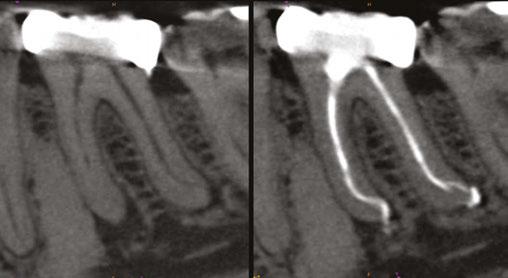

Figures 1A-1C: 1A. Preoperative X-ray. 1B. Immediate postoperative X-ray. 1C. Follow-up after 9 years and 10 months

Of the total, 29 had long-term radiographic follow-ups that ranged from a minimum of 6 months to a maximum of 25 years, with an average of 5 years, 4 months. Of the cases with radiographic follow-ups, 28 were considered successful and one failure (Table 2). Of the successful cases, 17 corresponded to treatments and 11 to retreatments (Figures 1A, 1B, 1C, and 2A, 2B, 2C). The tooth considered failed was a retreatment.

The radiographic appearances that generates the IRR are varied. The most common one observed in the present study was a circular shape with regular and symmetrical walls specially in single-rooted teeth (Figure 4A), although there were also some

Figures 2A-2C: 2A. Preoperative X-ray. 2B. Immediate postoperative X-ray. 2C. Follow-up after 18 years and 6 months

Figures 3A-3C: 3A. Preoperative X-ray. 3B. Immediate postoperative X-ray. 3C. Follow-up after 4 years

irregular ones with asymmetrical walls (Figure 4B). In molars, when resorption affects the pulp chamber, it was commonly seen as an irregularly shaped radiolucent cavity2 (Figure 4C).